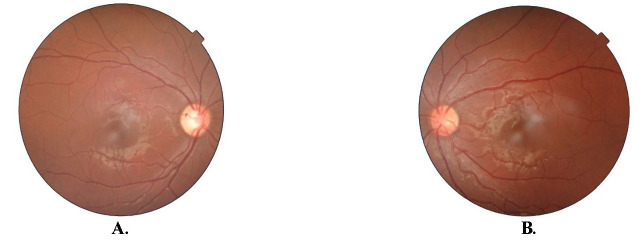

This case highlights the atypical presentation of Foster-Kennedy syndrome (FKS) associated with Neurocysticercosis (NCC), a prevalent cause of space-occupying lesions in areas endemic to the parasite. We report a newly diagnosed case of NCC in a 13-year-old boy who presented with a one-day history of abnormal movements of the left side of the body and no ocular complaints. Fundus examination of the patient revealed temporal disc pallor and a cup disc ratio (CDR) of 0.6 in the right eye suggesting unilateral optic disc atrophy and a hyperaemic disc with CDR 0.3 and blood vessel tortuosity in the left eye suggesting contralateral impending disc edema, mimicking the classic triad of FKS. He was diagnosed with NCC based on clinical features and radiological findings and was started on Carbamazepine (400 mg), Prednisolone (60 mg), Albendazole (400 mg), Acetazolamide (750 mg), and Vitamin B12 complex. Abbreviations: BCVA = Best Corrected Visual Acuity, CDR = Cup-Disc Ratio, CT = Computed Tomography, FKS = Foster Kennedy Syndrome, IDSA = Infectious Diseases Society of America, ICP = Intracranial Pressure, IOP = Intraocular Pressure, MRI = Magnetic Resonance Imaging, NCC = Neurocysticercosis, OOC = Orbital/Ocular Cysticercosis, OD = Right Eye, OS = Left Eye, OU = Both Eyes, RNFL = Retinal Nerve Fibre Layer, WNL = Within Normal Limits.